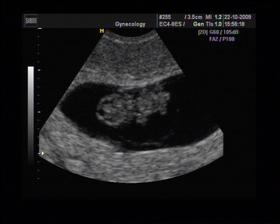

8/10 jsme se byli podívat u paní doktorky, zda testy nelhaly - a ono n e. Puclík měřil 0,37cm a co je důležité - srdíčko už funguje. Táta s Pepínem byli v ordinaci s námi, a když se na monitoru objevilo mimi, tak ho Pepíno pozdravil - udělal mu "ahoj" 🙂 oba nás to s Honzou dojalo. Další kontrola 22/10.